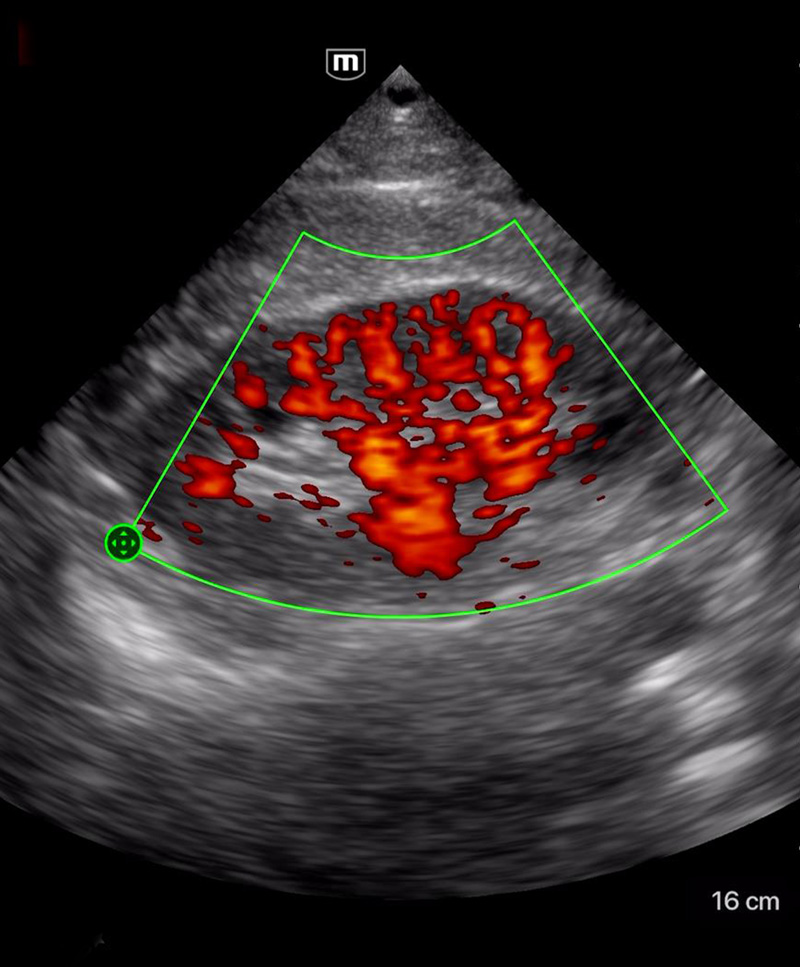

Immagini cliniche

Ascite

Cardiomiopatia dilatativa

Immagini cliniche

Ascite

Cardiomiopatia dilatativa